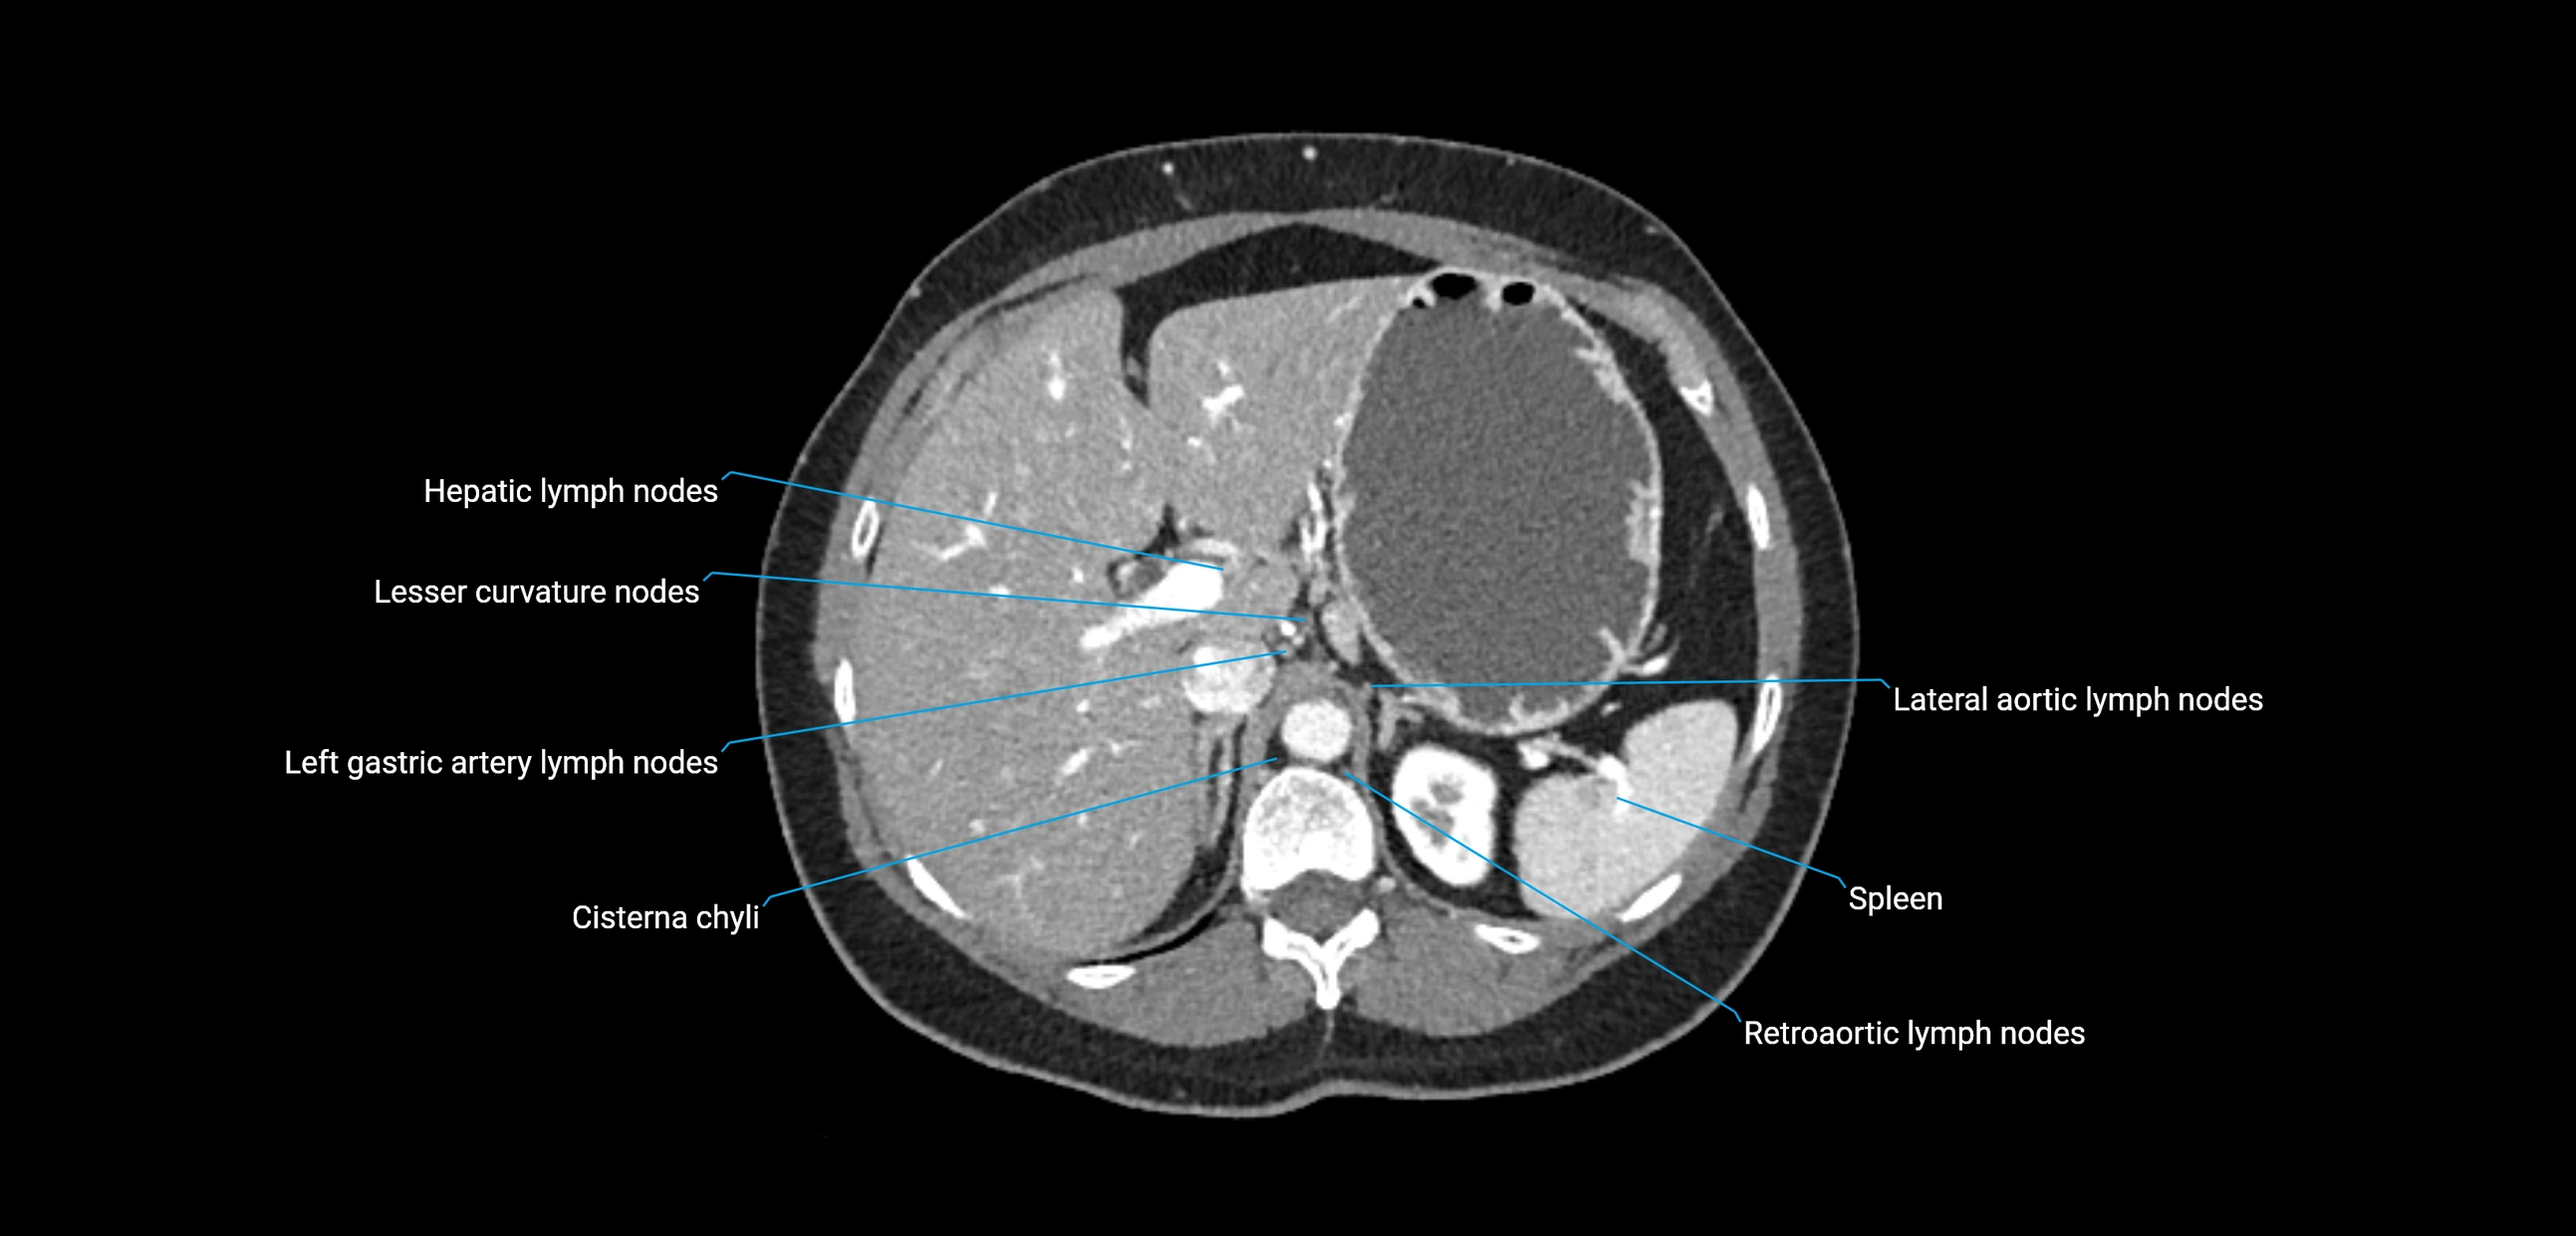

The lateral aortic lymph nodes (also called para-aortic lymph nodes) are a major group of retroperitoneal lymph nodes located along the abdominal aorta and its branches. They lie between the diaphragmatic crura superiorly and the bifurcation of the aorta at L4 inferiorly.

These nodes receive lymph from a wide range of abdominal and pelvic structures. Specifically, they drain lymph from the kidneys, suprarenal glands, gonads (testes/ovaries), uterus, uterine tubes, and pelvic organs, before converging into the lumbar lymphatic trunks, which terminate in the cisterna chyli → thoracic duct.

• Drain lymph from the kidneys, suprarenal glands, ureters, gonads, and pelvic organs

• Provide a major pathway to the cisterna chyli and thoracic duct

CT Appearance

CT Pre-Contrast:

• Nodes appear as soft-tissue density nodules adjacent to the aorta and IVC

CT Post-Contrast:

• Normal nodes enhance homogeneously

• Malignant nodes may show heterogeneous enhancement, central necrosis, or conglomerate formation

• Size >1 cm short axis is suspicious, though morphology and distribution are equally important